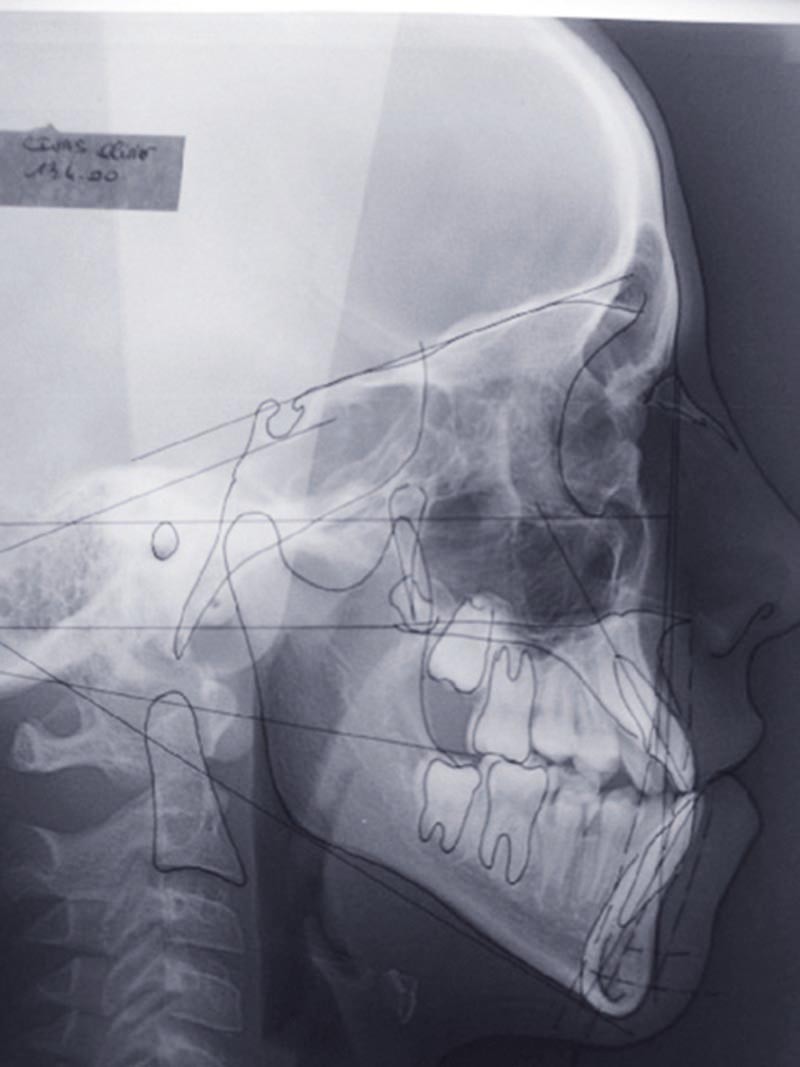

Les mouvements de décompensations sagittales et transversales sont réalisés à l’aide des tractions inter-arcades. La réévaluation céphalométrique et l’analyse des moulages confirment l’indication d’une chirurgie maxillaire de propulsion et d’une chirurgie mandibulaire par clivage bilatéral des branches montantes pour un recul mandibulaire modéré accompagné d’une génioplastie bidimensionnelle élargie qui rappelle la technique de Chin Wing.